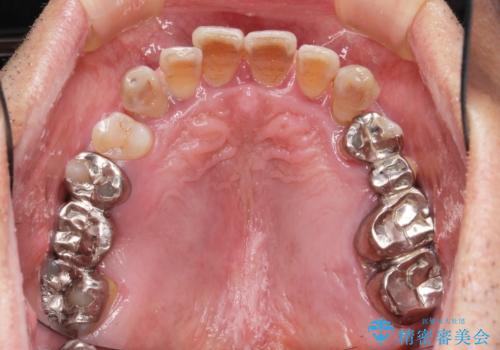

- 他院で上顎は全て抜歯し、入れ歯にする必要があると言われ相談に来院されました。

検査の結果、重度の歯周病であることから保存が難しい歯は抜歯を行いインプラントを、残すことが可能な歯には再生治療を含めた歯周病治療を行いより多くの歯を残す歯周病治療を計画します。